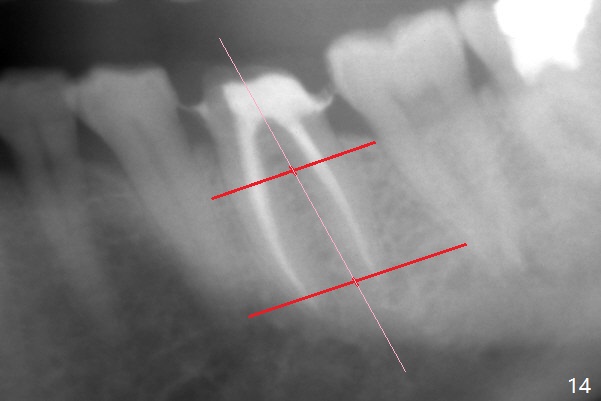

When the patient returns 9 months later, there is severe buccal gingival recession and abscess at #19 (Fig.1 *) with large mesial periradicular radiolucency (Fig.2 *).  The septum is thin and the buccal crest is low after extraction (Fig.3 * (mesial root vertical fracture)).  Osteotomy is initiated in the mesial socket immediately against the septum (Fig.4.5) with ~ 5 mm in the native bone.  Due to severe buccal plate resorption, a shorter implant is placed (Fig.6; 5x15 mm in stead of 18 mm).  There is at least 2 mm gap buccally for Vanilla Graft, which is also placed next to the implant and the neighboring root (Fig.7 *).  There is clearance from the Inferior Alveolar Canal (Fig.8 red dashed line).  Both the mesial and distal sockets heal 5.5 months postop (Fig.9), although the apical portion of the distal socket was not filled with allograft (Fig.7).  The implant was placed mesial.  The straight abutment (6.5x4(4) mm) (Fig.10) is changed to an angled one (5.5 x15 degrees 3 mm cuff (Fig.11)) before impression.  The implant is also placed buccally.  Therefore the implant position is far more important than its length.  The abutment is retightened 2.5 months post cementation, which is related to mesiobuccal placement of the implant (Fig.12).  An ideal trajectory is determined by drawing 2 horizontal lines (at crestal and apical levels: red lines in Fig.13), finding a central point of each line (vertical short line) and joining these 2 central points (Fig.14 pink line).  In fact the ideal osteotomy should have been established distal to the septum in this case.  Guided surgery may alleviate the issue.  The crown is not loose, but the patient feels that the implant tooth cannot sustain mastication.  In fact the screw is removed with hand driver (not wrench).  The abutment hex is rounded and worn.  A new 5.5x4(4) mm abutment is placed (without knowledge of previous use of an angled abutment) with mesial reduction to reduce undercut and buccodistal margin lowered to reduce gingival embrasure. It is that the straight abutment could decrease the chance of screw loosening.  Otherwise the implant has to be removed for better trajectory.